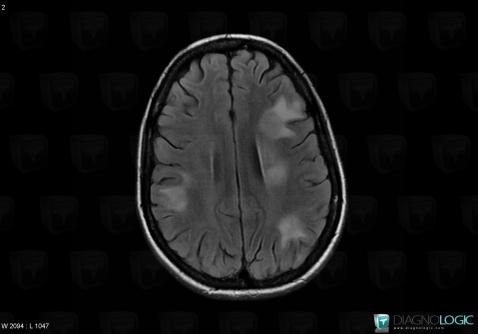

Toxoplasmosis, Basal ganglia and capsule, MRI

Here is the specific information in the key image above:

- Diagnosis Toxoplasmosis (link to Abscess), Location(s) Basal ganglia and capsule, with gamuts Basal ganglia T2W or FLAIR hyperintense lesion